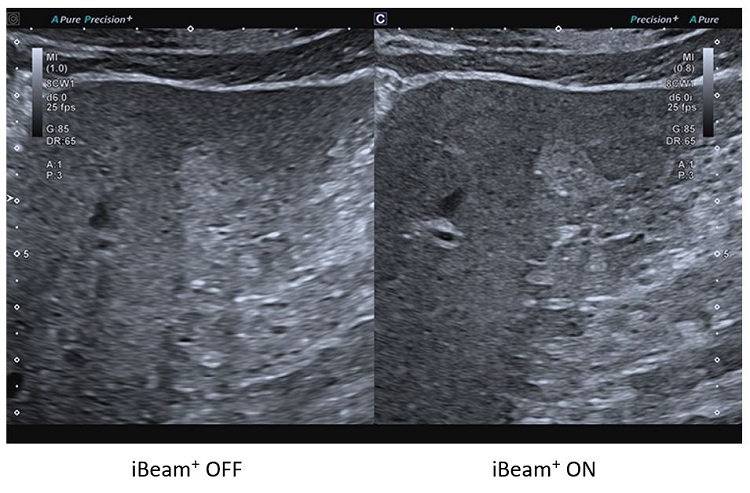

iBeam+

Особливі технології обробки зображень Aplio можуть допомогти покращити якість зображення шляхом зменшення шумів, посилення сигналу та покращення візуалізації.

Система обробки зображень iBeam+ використовує вдосконалену обробку сигналів для більш точного й гнучкого керування ультразвуковими променями, що робить зображення більш глибоким і чітким.